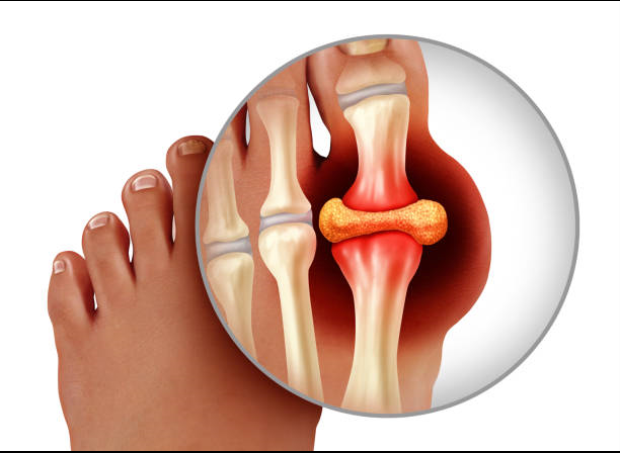

퓨린은 체내에서 분해되어 '요산'으로 전환되는데, '요산'이 과도하게 축적된다면 통풍의 증상이 나타나게 됩니다. 필수 아미노산 중 하나인 퓨린은 에너지로 사용된다면 체내에서 분해되어 '요산'으로 전환됩니다. 체내에 '요산'이 과도하게 축적된다면 통풍 증상이 나타나게 됩니다. 따라서 '요산'은 통풍의 원인과 가장 일반적으로 관련된 물질입니다.

체내 백혈구는 박테리아나 바이러스가 생성한 이 화학결합을 음식으로 인식하고 염증 반응 물질을 터뜨려 매우 심한 염증과 통증을 유발합니다. 식습관과 밀접한 관계가 있는 통풍을 예방하기 위해서는 새우젓, 동물 창자 등 퓨린이 많이 함유된 음식과 요산 배설 장애를 일으킬 수 있는 맥주를 피하는 것이 중요하다.

그 후, 손, 무릎, 발목의 관절에 계속해서 영향을 줄 수 있습니다. 통풍의 증상은 시기에 따라 고요산혈증, 급성 통풍성 관절염, 간헐성 통풍의 3단계로 분류할 수 있습니다. 일반적으로 엄지발가락 관절의 갑작스러운 종창이 처음 징후이며, 곧 해당 부위에 극심한 통증과 발적이 뒤따릅니다. 관절이 뜨거워져 신발을 신을 수 없게 될 수 있습니다. 그리고 손, 무릎, 발목의 관절에도 연속적으로 영향을 미칠 수 있다.